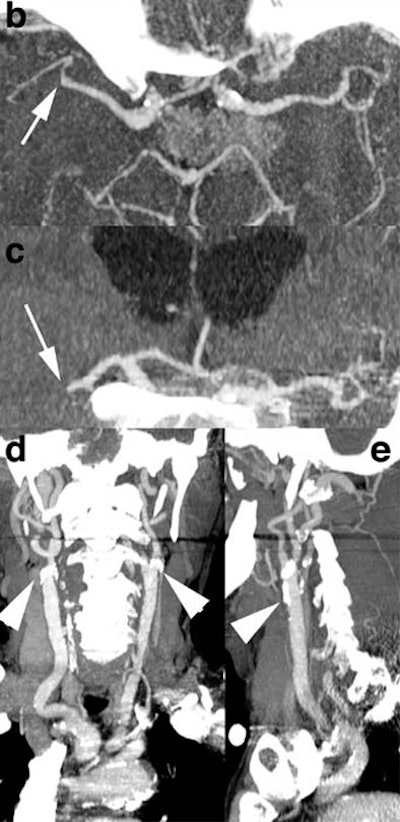

| Above: a) Admission perfusion CT demonstrates mixed infarct and penumbra in the left sylvian territory in a patient with a right hemisyndrome, whereas b) CT angiography (CTA) relates it to an occlusion at the left M1-M2 junction (arrow). The patient underwent intravenous thrombolysis and his clinical condition evolved favorably. Twenty-four hours after admission, d) follow-up CTA features a recanalization of the left sylvian artery, later confirmed on f) MR angiography (MRA). c) Follow-up perfusion-CT shows an almost complete resolution of the penumbra, afforded by the early arterial recanalization. The final perfusion CT infarct has progressed only in a very limited fashion compared to the admission perfusion CT infarct; its extent closely correlates with the abnormality on e) delayed DWI trace image. Images courtesy of Dr. Max Wintermark. |